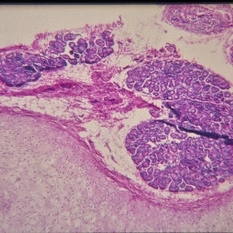

Histopathology of Linear Sebaceous Nevus Syndrome

Histopathology of Linear Sebaceous Nevus Syndrome

Feb 20 2015 by H. Michael Lambert, MD

Histopathology of linear sebaceous nevus syndrome.

Condition/keywords: histopathology, linear nevus sebaceous syndrome

-

Histopathology of Linear Sebaceous Nevus Syndrome

Histopathology of Linear Sebaceous Nevus Syndrome

Feb 20 2015 by H. Michael Lambert, MD

Histopathology of linear sebaceous nevus syndrome.

Condition/keywords: histopathology, linear nevus sebaceous syndrome

-

Histopathology of Linear Sebaceous Nevus Syndrome

Histopathology of Linear Sebaceous Nevus Syndrome

Feb 20 2015 by H. Michael Lambert, MD

Histopathology of linear sebaceous nevus syndrome.

Condition/keywords: histopathology, linear nevus sebaceous syndrome